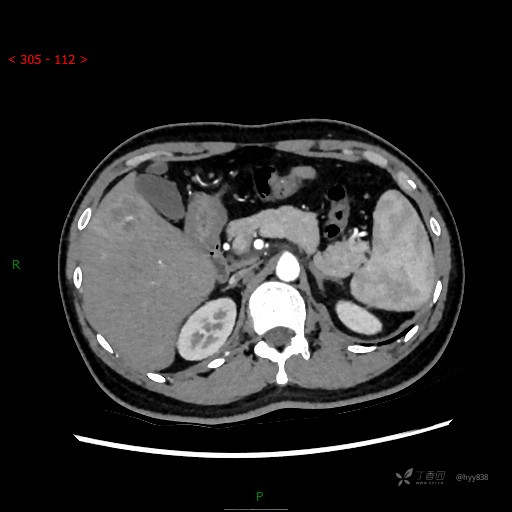

肝脏CT平扫